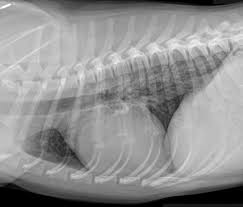

Dog With Lung Cancer Coughing : Chronic Bronchitis Canine Mar Vista Animal Medical Center : This is how my dog breathed with lung cancer.. The most common abnormal clinical sign reported in dogs with lung cancer is chronic cough. Metastatic lung cancer migrates to the lungs from other parts of the body through the bloodstream and is more common, especially in dogs over ten years. This is how my dog breathed with lung cancer. One of the most common reasons for a dog cough is a disease of the heart valves or heart muscle; While both primary lung cancer and metastatic lung cancer have similar symptoms, coughing tends to be less common with metastatic tumors.

Bronchitis In Dogs Symptoms Causes Diagnosis Treatment Recovery Management Cost from images.wagwalkingweb.com If the dog coughs once or twice, it's of no concern, but if it continues to cough for more than a few days, that's a concern and could signal lung cancer, says zaidel. Coughing end stage lung cancer in dogs will cause the coughing to progress. These canine cough home remedies are also good for treating kennel cough. Chronic coughing seems to be the most common abnormality that is seen in dogs with lung cancer. But it's rare that a chronic cough in your dog will be a sign of lung cancer. We examine the onset, diagnosis, and the cancer treatment combination that is curing simon of bone cancer. Stage 2 lung cancer will manifest through the growth of several smaller tumors that won't exceed 5 cm in length. Allergic lung disease and lung cancer.

The most common sign of lung cancer in dogs is a chronic cough.

In the late spring of 2019, my wife noticed a small lump about the size of a grape on the. The dog is not coughing up mucus) although the cough may produce small amounts of phlegm or blood. What are the signs of lung cancer in a dog? He is almost 14 yrs old and has been struggling with his appetite for about 3 weeks and also has a minor cough occasionally. Some small breeds of dogs may develop a cough due to problems with their windpipes. Anyone dealing with canine osteosarcoma dreads the cough that typically accompanies osteosarcoma lung metastasis. Occasionally pets will cough up small amounts of blood or phlegm. Adenocarcinoma tumors in dogs start out as abnormal growths in the epithelial tissue layer. Bronchitis is a dry hacking cough with wheezing and gagging. Coughing results when parts of the heart enlarge and compress the major airways in the lungs, or when fluid backs up into the lungs. As a matter of fact, almost 80% of primary lung cancer is caused by adenocarcinoma. Or it may be because of congestive heart failure. The cough is unproductive (not coughing up mucus), but sometimes the dog may cough up blood.

However, sometimes a cough can be a sign of lung cancer in dogs. It hurts, and feels hopeless, but it's important to remember that it's not necessarily the end of the journey. Other common symptoms of cancer, including weight loss, inappetence, vomiting and diarrhea, might also occur. Adenocarcinoma tumors in dogs start out as abnormal growths in the epithelial tissue layer. A cough here and there, once or twice, isn't a concern. This is a malignant neoplasm, with the ability to grow rapidly and metastasize to distant parts of the body, including the organs, lymph nodes, bones, brain and eyes. Primary lung cancer is rare. Adenocarcinoma of the lung in dogs adenocarcinoma of the lung makes up about 75 percent of all primary lung tumors in dogs. Symptoms of lung cancer in dogs usually there are no symptoms in the early stages of canine lung cancer. Pulmonary tumors description — primary lung cancer may arise from any part of the lung but neoplasm of the conducting airways or alveolar parenchyma (functional part of the lungs consisting of the alveoli) are the most common.it accounts for 1% of all neoplasms reported in dogs. The most common complication of lung cancer in dogs is fluid buildup in the lungs, or pleural effusion. Sometimes a tumor can be quite He is almost 14 yrs old and has been struggling with his appetite for about 3 weeks and also has a minor cough occasionally.